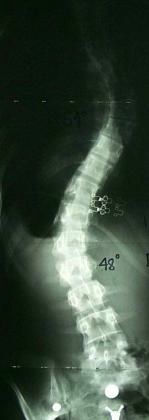

Искривление позвоночника

Искривления позвоночника — изменения нормальной конфигурации позвоночника. Позвоночник взрослого правильно сложенного человека имеет характерные изгибы: в шейном отделе позвоночник отклонен выпуклостью вперед (шейный лордоз), в грудном отделе — вперед (поясничный лордоз) и в крестцовом отделе — назад. Изгибы позвоночника формируются в детском возрасте. Боковых изгибов нормальный позвоночник не имеет.

Искривления позвоночника могут возникать при нарушениях внутриутробного развития скелета — образование клиновидных и добавочных позвонков, неправильное формирование 5 –го поясничного позвонка и ребер и т. п. Это т. наз. врожденное искривление. Иногда же оно возникает вследствие какого-нибудь заболевания (рахит, полиомиелит, туберкулез и др.), травм (переломы позвоночника), при нарушениях правильного стояния , при разной длине нижних конечностей и пр. В более позднем возрасте, уже после окончания формирования скелета, искривления позвоночника развиваются у лиц канцелярского труда, скрипачей, сапожников и др., труд которых связан с длительным пребыванием в одной позе. Большую роль в их образовании играет мышечная система. При развитии деформации позвоночника нарушается равномерная тяга мышц, окружающих позвоночник, что в свою очередь усугубляет уже имеющееся искривление.